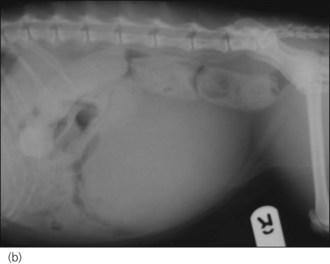

Respiratory distress: brain injury can give rise to neurogenic (non-cardiogenic) pulmonary oedema that usually develops within minutes to a few hours of the event. Thoracic radiographs typically show a caudodorsal distribution of lung field changes consistent with pulmonary oedema (interstitial to alveolar pattern) (Figure 28.1). Treatment involves oxygen supplementation and minimal stress; neurogenic pulmonary oedema is likely to be of mixed cause and a single low dose of furosemide may be rational. Clinical improvement is typically noted within 24–48 hours.

image

Figure 28.1 Thoracic radiograph of a puppy with head trauma showing caudodorsal lung changes consistent with neurogenic (noncardiogenic) oedema.